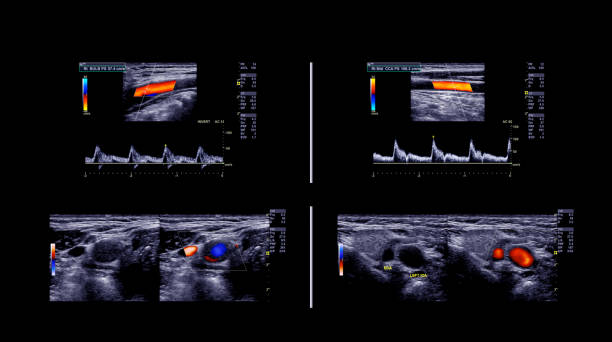

경동맥 초음파 검사로 알수있는병 - 검사 결과 해석

검사 결과를 해석할 때, 의사는 다음 사항을 고려합니다.

- 경동맥의 크기와 형태: 경동맥이 충분히 넓고 매끄럽게 유지되는지 확인합니다.

- 혈류 속도: 혈액이 경동맥을 흐르는 속도를 측정하여 혈액순환에 이상이 없는지 확인합니다.

- 혈액 응고물질의 존재: 콜레스테롤과 혈액 응고물질이 경동맥 벽에 쌓여 있는지 확인합니다.